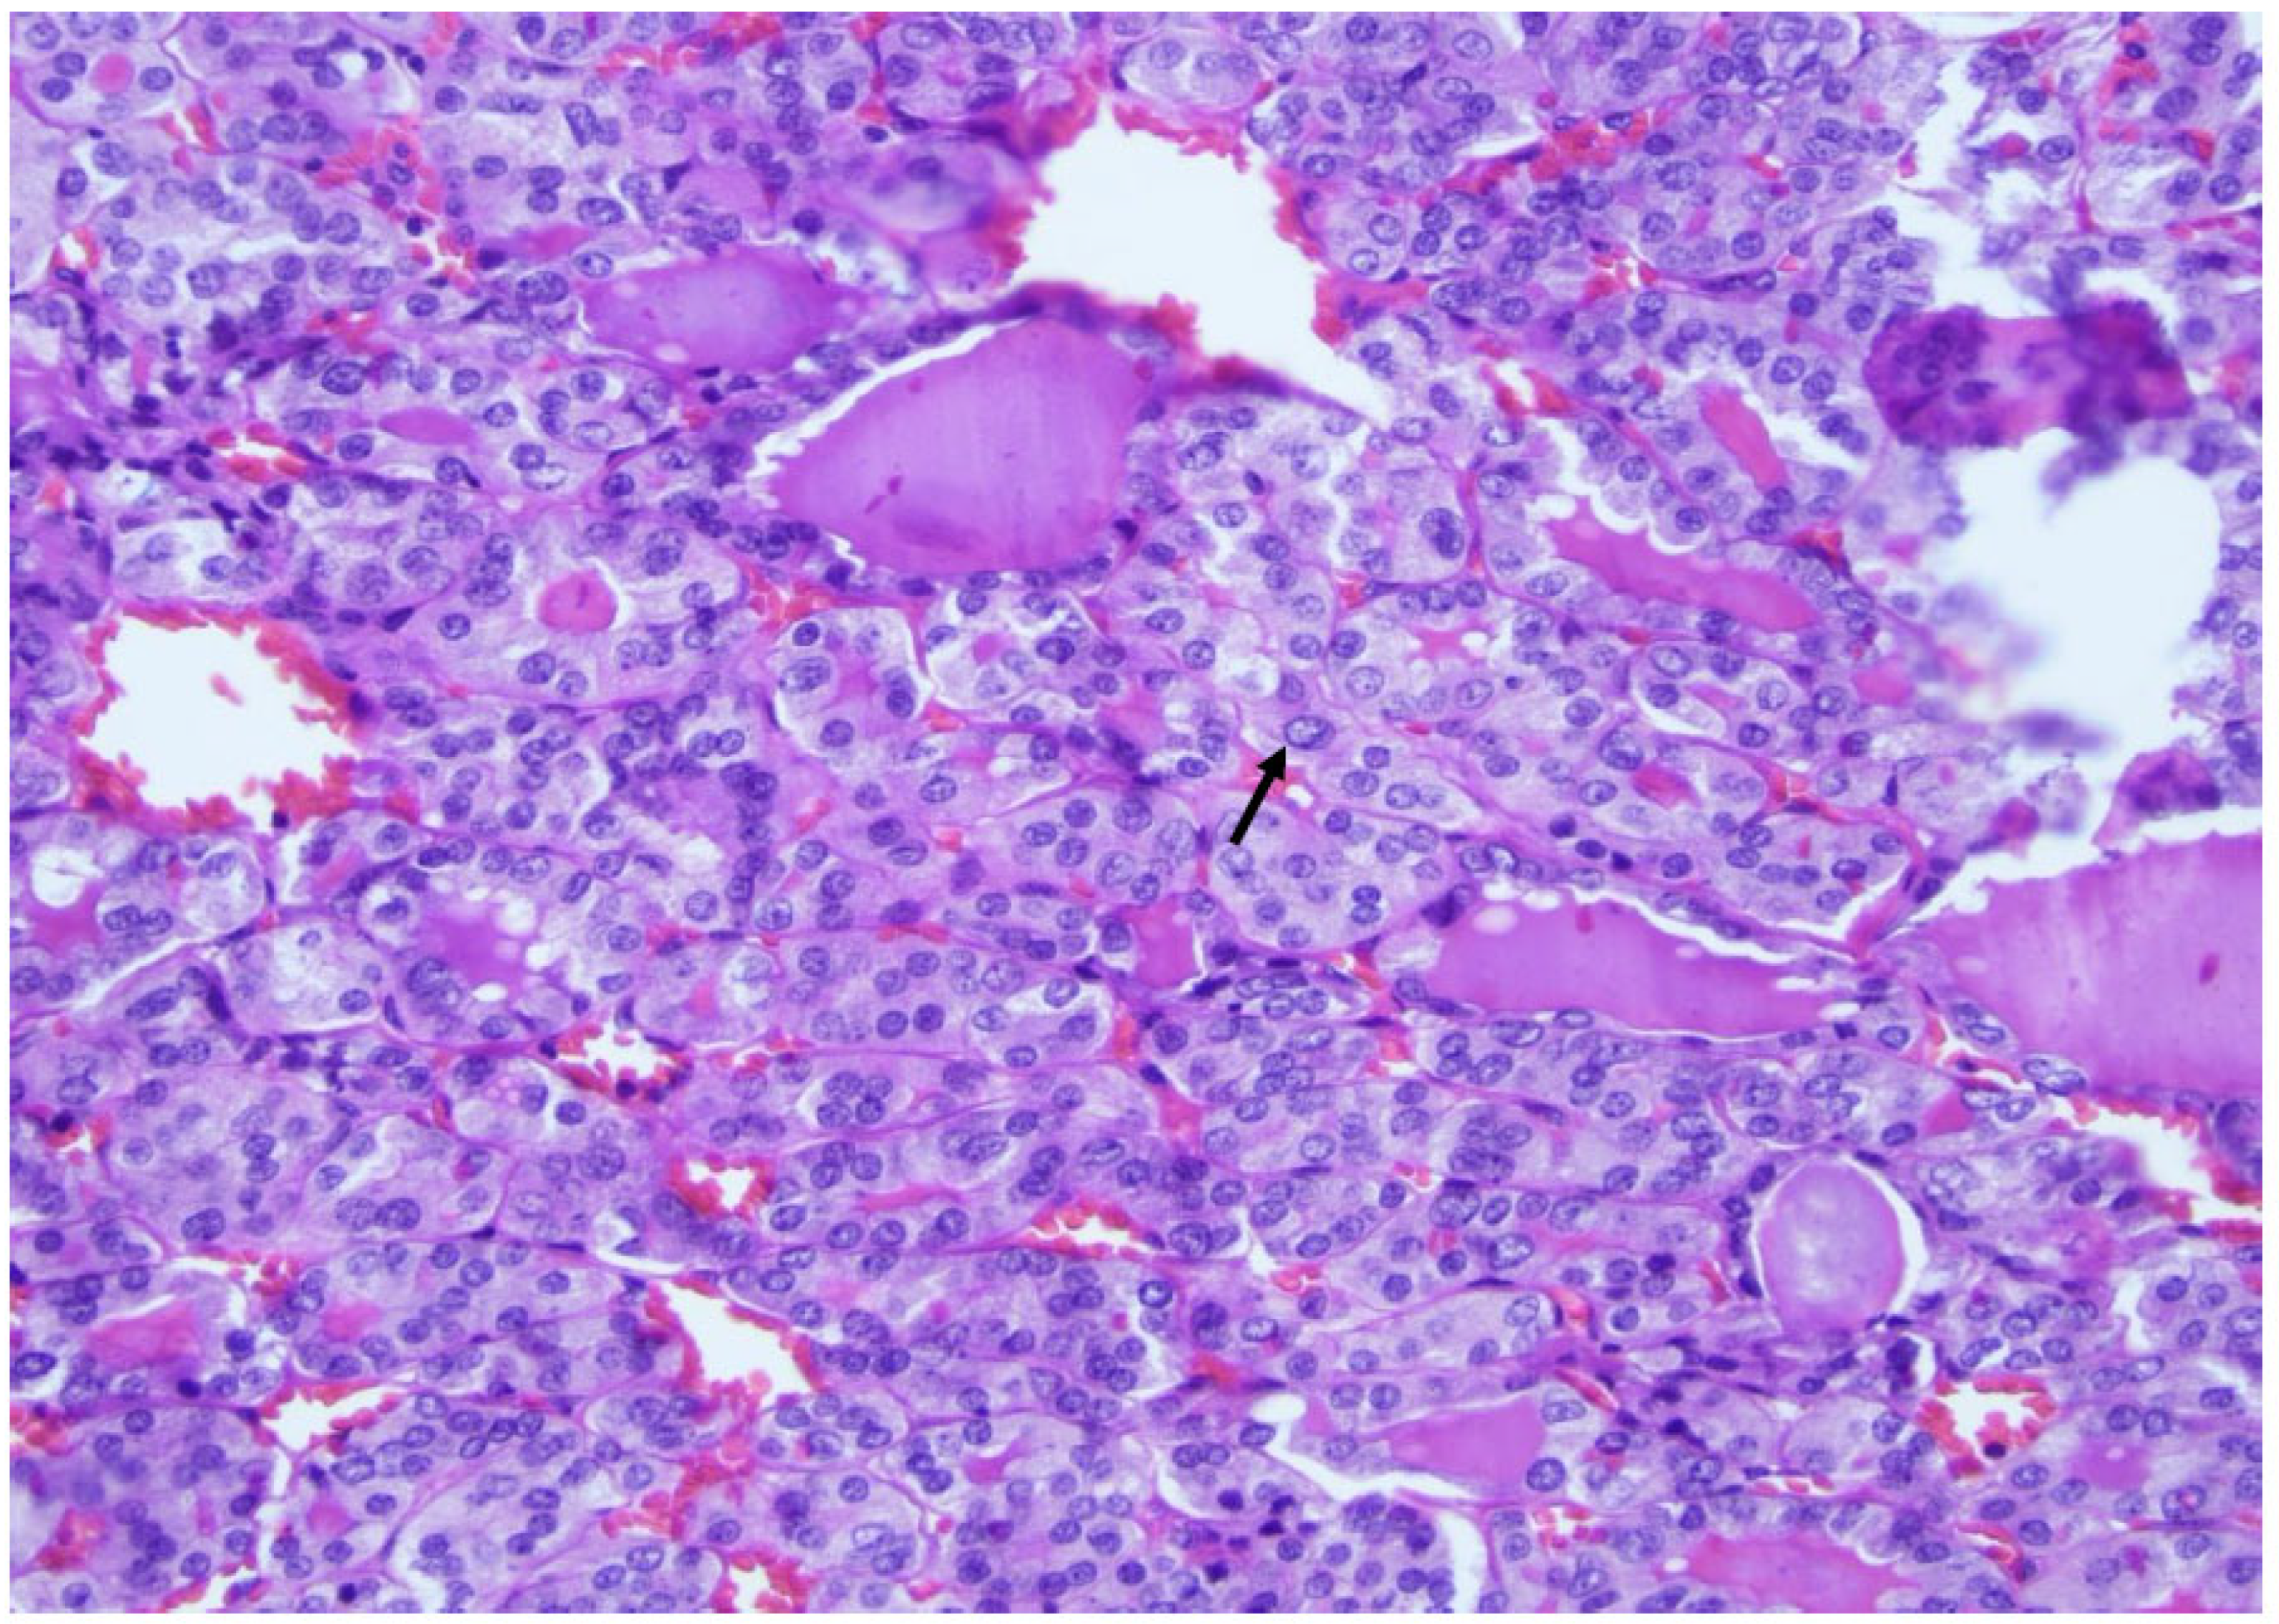

Figure 10. Medullary thyroid carcinoma at a higher magnification: note the mitosis (arrows), indicating a high-grade medullary carcinoma diagnosis (×200, H&E stain).

The most significant update for medullary thyroid carcinoma (Figure 9) is the introduction of a grading system called “the International medullary thyroid carcinoma grading scheme”. This is a two-tiered grading system; high-grade cancers are characterized by tumor necrosis; a mitotic count ≥ 5 mitoses per 2 mm2; and/or a Ki 67 proliferation index ≥ 5% (Figure 10 and Figure 11) [10].